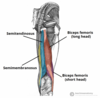

What is this muscle?

What is this muscle?